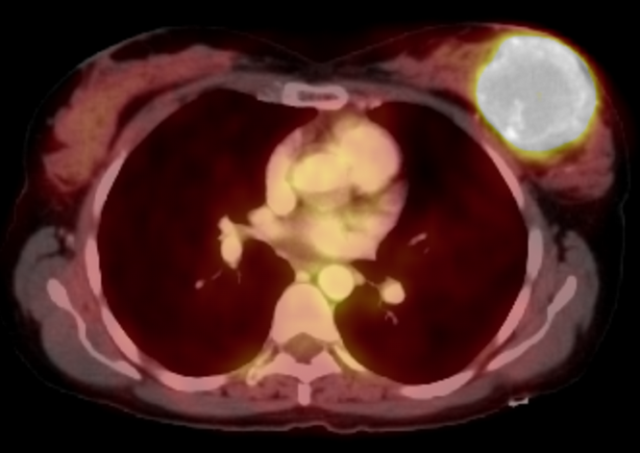

Case: Breast Sarcoma Figure 1

Figure 1: 45-year-old female presented with an enlarging palpable mass. Craniocaudal (A), mediolateral oblique (B), and mediolateral (C) mammographic views of the left breast demonstrate heterogeneously dense breast tissue with an approximately 6-centimeter round mass with partially circumscribed and partially obscured margins adjacent to an overlying skin BB marker. Tissue diagnosis resulted in undifferentiated high grade spindle cell sarcoma.

There are no pathognomonic imaging features for breast sarcoma on any imaging modality and imaging findings are widely variable. Mammographically, breast sarcomas are described as round, oval, or irregular masses with microlobulated or indistinct margins3. They demonstrate high density compared to the surrounding breast fibroglandular tissue (Figure 1). A less common mammographic finding is architectural distortion, and there are infrequently associated microcalcifications. In fact, the lack of microcalcifications may serve as a clue to include sarcoma in the differential diagnosis1,4.